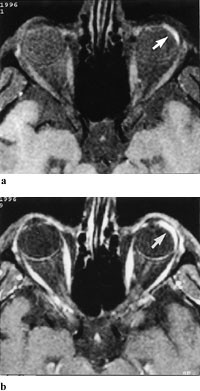

Ved mistanke om retinoblastom utføres først oftalmoskopi og ultralydundersøkelse. Hvis ultralydundersøkelsen ikke viser kalk, bør CT gjøres (fig 3). Hvis ultralydundersøkelse eller CT viser kalk, bør MR utføres for å avgjøre om det er ekstraokulær utbredelse av tumor (fig 4), samt vise dette i forhold til n. opticus og orbita (5). Ved bilaterale eller familiære retinoblastomer er MR indisert for å utelukke eller påvise asymptomatisk midtlinjemalignitet, såkalt pinealoblastom (6).